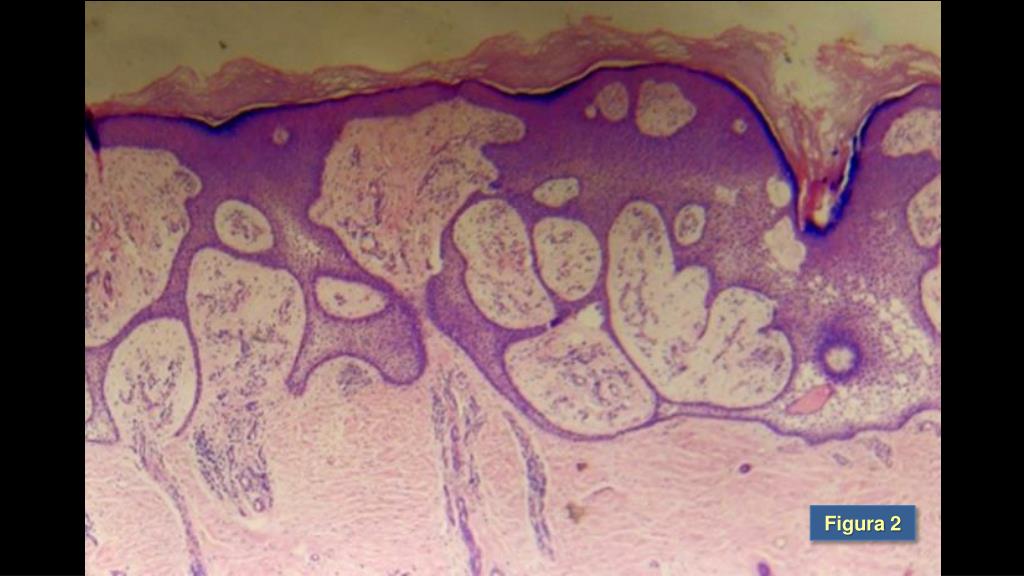

3. RELATO DE CASO • Paciente do sexo masculino, 75 anos, pardo, casado, aposentado, natural e residente no Rio de Janeiro. • Encaminhado ao Serviço de Dermatologia com queixa de “feridas” no pé esquerdo que surgiram após quadro de erisipela bolhosa no membro referido, quatro anos antes da consulta inicial. • HPP: hipertensão arterial sistêmica, Diabetes Mellitus tipo 2, insuficiência renal crônica, retinopatia diabética, bloqueio atrioventricular total (PACE definitivo). • Ao exame: Lesão em placa de 17 cm de diâmetro, com bordas elevadas de aspecto verrucoso e centro atrófico, com área ceratósica central no dorso do pé esquerdo (Figura 1). • Exame histopatológico da lesão revelou delgadas trabéculas anastomosantes de células discretamente basalóides, imersas por tecido conjuntivo frouxo contendo vasos ectasiados e congestos, compatível com Siringofibroadenoma (Figura 2).

5. Figura 2